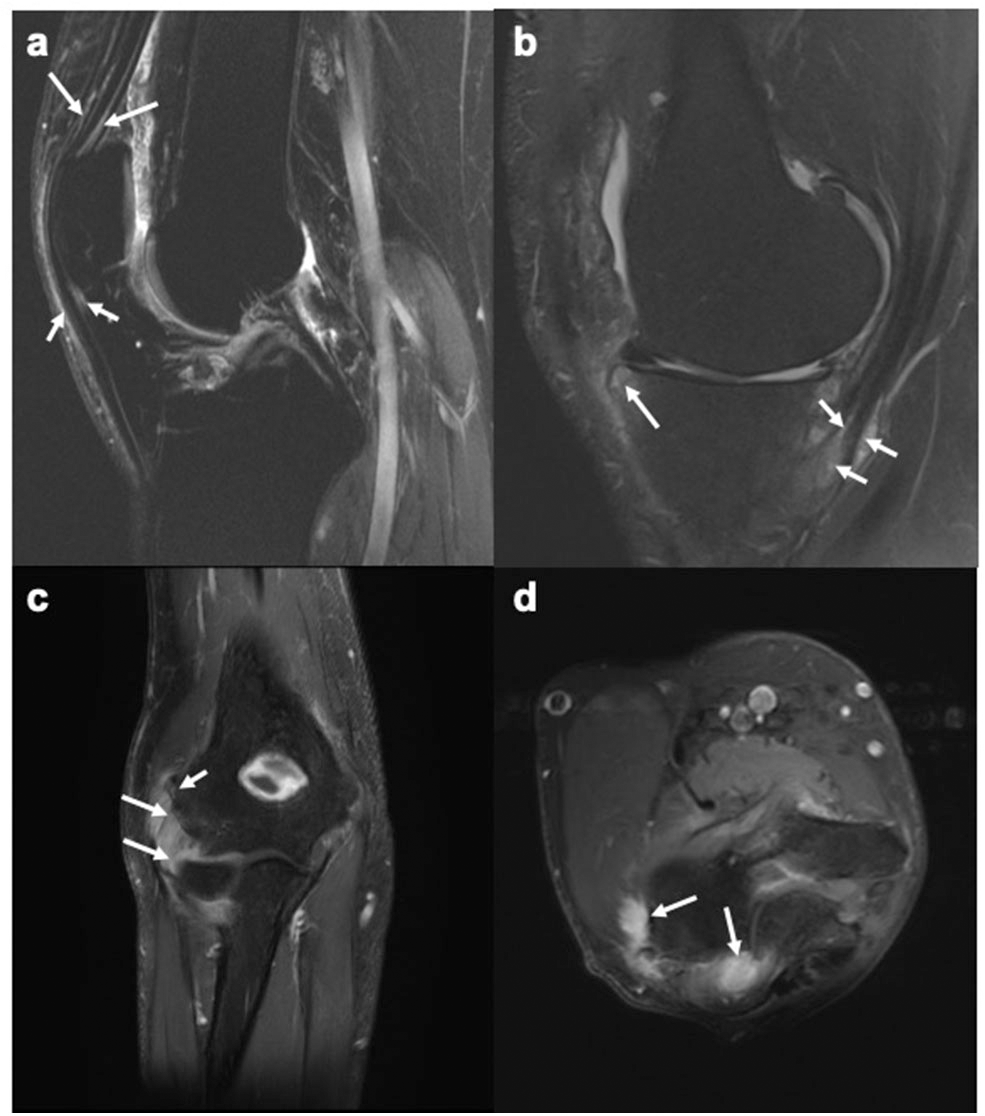

Given the avascular nature of the entheses at bony attachment sites and low density of vessels in the surrounding ligaments and tendons, diagnosis of enthesitis with imaging can be demanding (14). MRI has the unique advantage of identifying peri-entheseal inflammation with adjacent bone marrow edema, potentially facilitating early diagnosis in SpA (23) (Figures 1a–d). Fat-suppressed MRI with or without gadolinium enhancement is the most sensitive method of visualizing active enthesitis (24, 25). The European Society of Musculoskeletal Imaging (ESSR) arthritis subcommittee for the use of MRI has suggested specific sequences based on the area to be examined for inflammatory changes (26). The OMERACT MRI in enthesitis initiative proposes T1weighted post gadolinium sequence for entheseal soft tissue inflammation, STIR/T2weighted fat suppressed sequence for entheseal osteitis, and T1 weighted pre-gadolinium sequence for entheseal structural changes (27). MRI is useful in diagnosing enthesitis in the appendicular and axial skeleton. Bone marrow edema (BME) in PsA is often located close to the entheses, as compared to capsular attachments and subchondral areas in RA and OA, respectively (28).

Figure 1. MR images of the knee and elbow depicting enthesitis. (a) Sagittal STIR image of the knee showing soft tissue high signal intensity (intra- and peritendinous) at the insertions of the quadriceps tendon (long arrows) and the patellar ligament (short arrows) at the patella, suggesting enthesitis. (b) Sagittal T2-weighted fat suppressed image of the knee showing high signal intensity (intra- and peritendinous) in the soft tissues of the pes anserine (short arrows), indicating pes anserine enthesitis, as well as bone marrow edema (long arrows) close to the insertion of the medial patellar retinaculum at medial tibial plateau. (c,d) Coronal (c) and axial (d) STIR images of the elbow showing bone marrow edema (mild, short arrow) and soft tissue high signal intensity (long arrows) at the common extensor tendon insertion at the lateral epicondyle, indicating enthesitis. Images courtesy of Professor Iris Eshed, Sackler School of Medicine, Tel Aviv University, Tel Aviv, Israel.